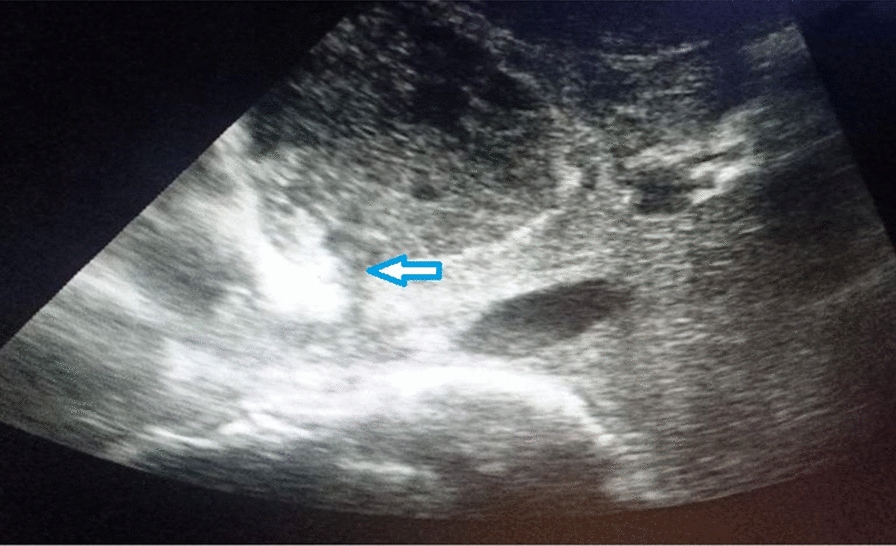

Case presentation: A 45-year-old Indian male presented with multiple episodes of fever with chills, palpitations, dyspnea, right upper abdominal pain, bilateral lower limb edema, and petechia for 20 days. On examination, tachycardia, tender hepatomegaly, and reduced air entry in the right lower lobe of the lung were observed. Ultrasound revealed an abscess in the left lobe of the liver about 150 cc in volume, abutting the inferior vena cava with rupture into it. Contrast-enhanced computed tomography imaging showed 5.7 × 6.2 × 5.4 cm segment IV A liver abscess with capsule breach into the intrahepatic vena cava and thrombus extending up to the right atrium was observed. Computed tomography-pulmonary angiography revealed a right atrium thrombus with bilateral pulmonary artery thrombus and parenchymal infarcts. Raised D-dimer, protein C and S deficiency was observed. The patient was managed by needle aspiration of abscess, anticoagulation, and antibiotics.